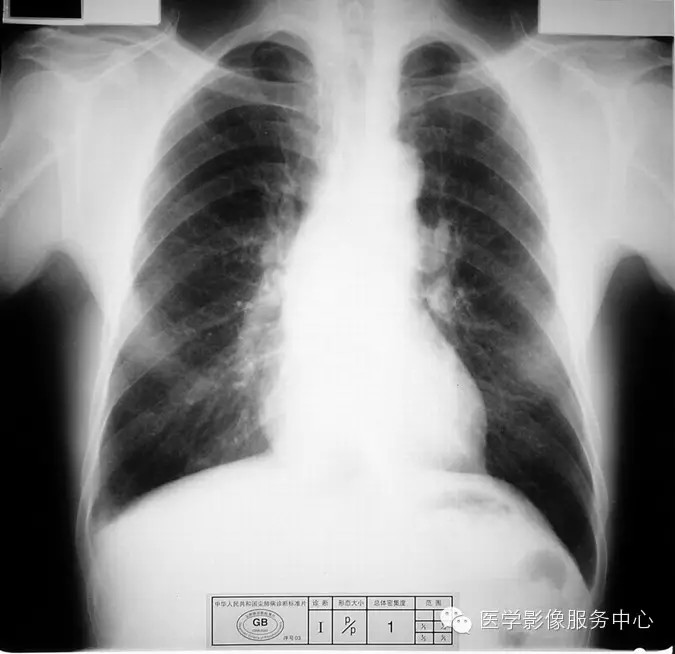

4.2 一期尘肺(Ⅰ)

a)Ⅰ:有总体密集度1级的小阴影,分布范围至少达到两个肺区。

b)Ⅰ :有总体密集度1级的小阴影,分布范围超过4个肺区或有总体密集度2级的小阴影,分布范围达到4个肺区。